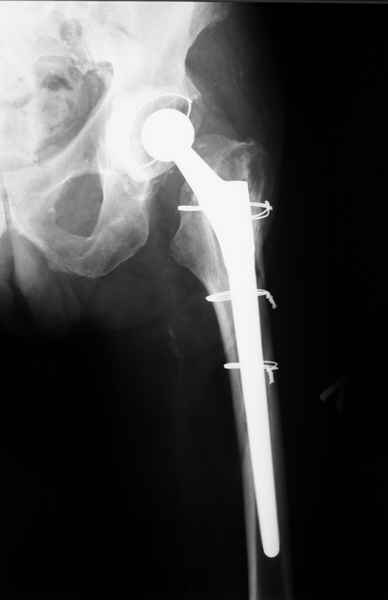

Уважаемые коллеги, продолжая дискуссию, начатую на "Вреденовских чтениях", хочу сказать, что принципиально сущестует два возможных варианта лечения.

1.Остеосинтез на ножке. Мне кажется, что применительно к этому случаю малоперспективный вариант. Синтез хорош, когда можно его выполнить в малоинвазивном исполнении и достигнуть стабильности. Действительно, если ножка б/цементной фиксации после этого не будет иметь фиксации, то ревизия не будет иметь проблем. В представленном случае стабильность синтеза сомнительная, а проведение доп.иммобилизации приведет к контрактуре суставов.

2. Применение ножки дистальной фиксации, мы отдаем предпочтение ножке Вагнера с фиксацией проксимального отдела на ножке. Более травматичное вмешательство, но при стабильной фиксации ножки реабилитация идет в обычном режиме.

Хочется показать два подобных случая, П-ка З. 72 лет и п-т Г. 80 лет. Сразу принимаю замечание, что это были ножки цементной фиксации, просто под руками не было бесцементника.

С уважением, Р.Тихилов